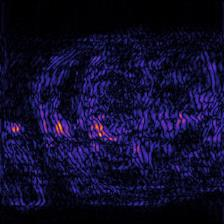

Recently, deep neural networks have greatly advanced undersampled Magnetic Resonance Image (MRI) reconstruction, wherein most studies follow the one-anatomy-one-network fashion, i.e., each expert network is trained and evaluated for a specific anatomy. Apart from inefficiency in training multiple independent models, such convention ignores the shared de-aliasing knowledge across various anatomies which can benefit each other. To explore the shared knowledge, one naive way is to combine all the data from various anatomies to train an all-round network. Unfortunately, despite the existence of the shared de-aliasing knowledge, we reveal that the exclusive knowledge across different anatomies can deteriorate specific reconstruction targets, yielding overall performance degradation. Observing this, in this study, we present a novel deep MRI reconstruction framework with both anatomy-shared and anatomy-specific parameterized learners, aiming to "seek common ground while reserving differences" across different anatomies.Particularly, the primary anatomy-shared learners are exposed to different anatomies to model flourishing shared knowledge, while the efficient anatomy-specific learners are trained with their target anatomy for exclusive knowledge. Four different implementations of anatomy-specific learners are presented and explored on the top of our framework in two MRI reconstruction networks. Comprehensive experiments on brain, knee and cardiac MRI datasets demonstrate that three of these learners are able to enhance reconstruction performance via multiple anatomy collaborative learning.